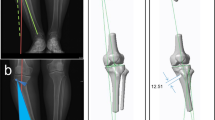

Following the final checks by the senior author and surgeon, the simulated osteotomy and correction were made using the Bodycad Osteotomy software. The WBL (weight-bearing line) correction to 55% of the tibial plateau width was chosen. An opening of 10.21 mm was calculated by the software to obtain this particular correction. The resulting patient’s lower limb alignment was calculated to be a tibiofemoral valgus alignment of 1.69° and a MPTA of 91.86°, with no change of the tibial slope (Figs. 3, 4). The hinge axis was planned to be at an ideal position of 15 mm from the lateral plateau and 10 mm from the lateral cortex. A biplane cut was proposed due to the tibial tuberosity that was in the way of the osteotomy cutting plane. The cut was positioned just below the ACL screw (Fig. 5). Approval of the pre-operative planning was done prior to manufacturing the patient-specific surgical guide and plate (Figs. 6, 7 and 8).

At 6-week follow-up, the patient’s range of motion was full extension to 125° of flexion with a well-healed incision and minimal pain. The patient was using acetaminophen as needed for pain. He was continuing with a physical therapy protocol. Radiographs taken at this 6-week visit demonstrated a satisfactory stage of healing, with a precise correction in the coronal and sagittal planes (Fig. 18). The angular correction of the bone was achieved within 1.9° (planned MPTA 91.9° vs. actual 90°); the HKA angle was achieved with an error of 0.7° (planned 2.4° vs. actual 1.7°); and there was no change in the posterior tibial slope (planned 13.5° vs 13.8° actual) (Fig. 19).